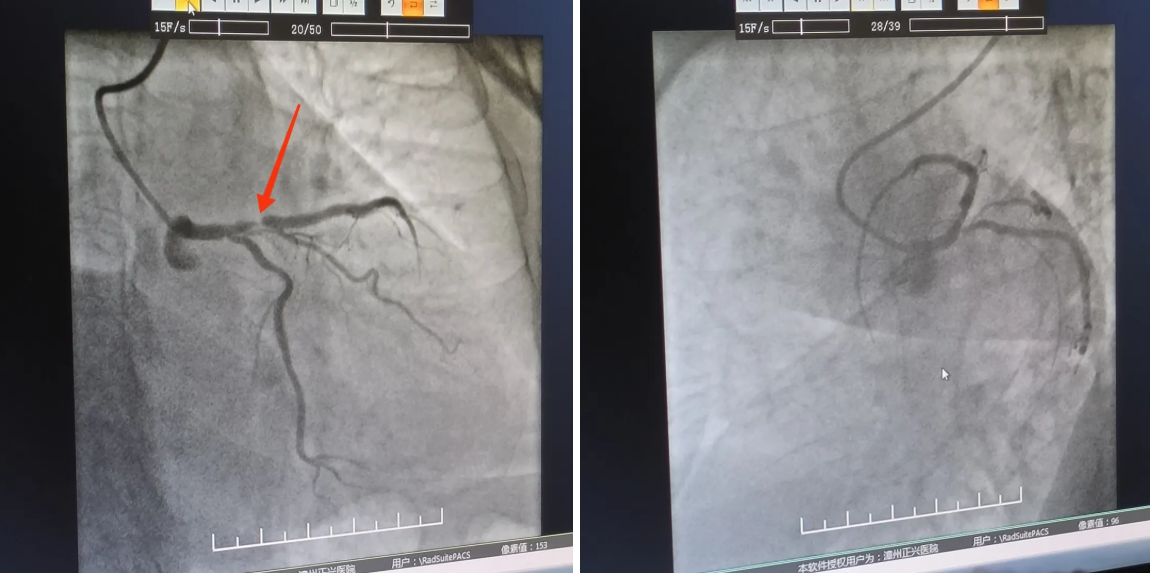

曾丁邻主刀医师与查庆春医师默契配合,迅速完成冠脉造影定位狭窄病变,可见:左主干末端至前降支近段支架以弥漫性偏心性病变,狭窄程度最高达 90%,回旋支开口管状偏心病变,最重狭窄 60%。

『开通前』

术中,介入团队于毫厘之间如穿针引线般将导丝送入狭窄病变处,随即送预扩球囊把左主干-前降支病变扩张开。

看到扩张后病变部位狭窄明显减轻,一鼓作气成功植入一枚支架,医护人员如释重负,解除了一枚「定时炸弹」,悬着的心终于放下了。